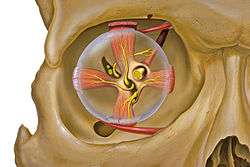

Eye and orbit anatomy with motor nerves